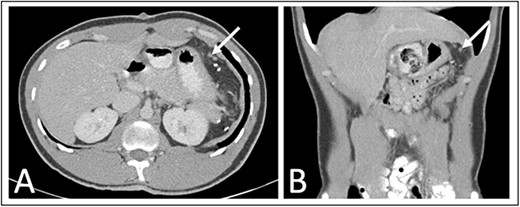

As part of his workup, he underwent an abdominal ultrasound showing a 12 cm cystic or hemorrhagic lesion, likely splenic in origin, with an adjacent 5.6 cm complex septated lesion within the spleen. Subsequent abdominal CT showed a 12 cm in greatest diameter complex cystic lesion within the spleen with peripheral and septal calcification with no solid enhancing component (Fig. 1). His blood work, including complete blood count, complete metabolic panel, and coagulation markers, were all within normal limits.

Preoperative (A) axial and (B) coronal abdominal CT images showing complex cystic splenic mass.